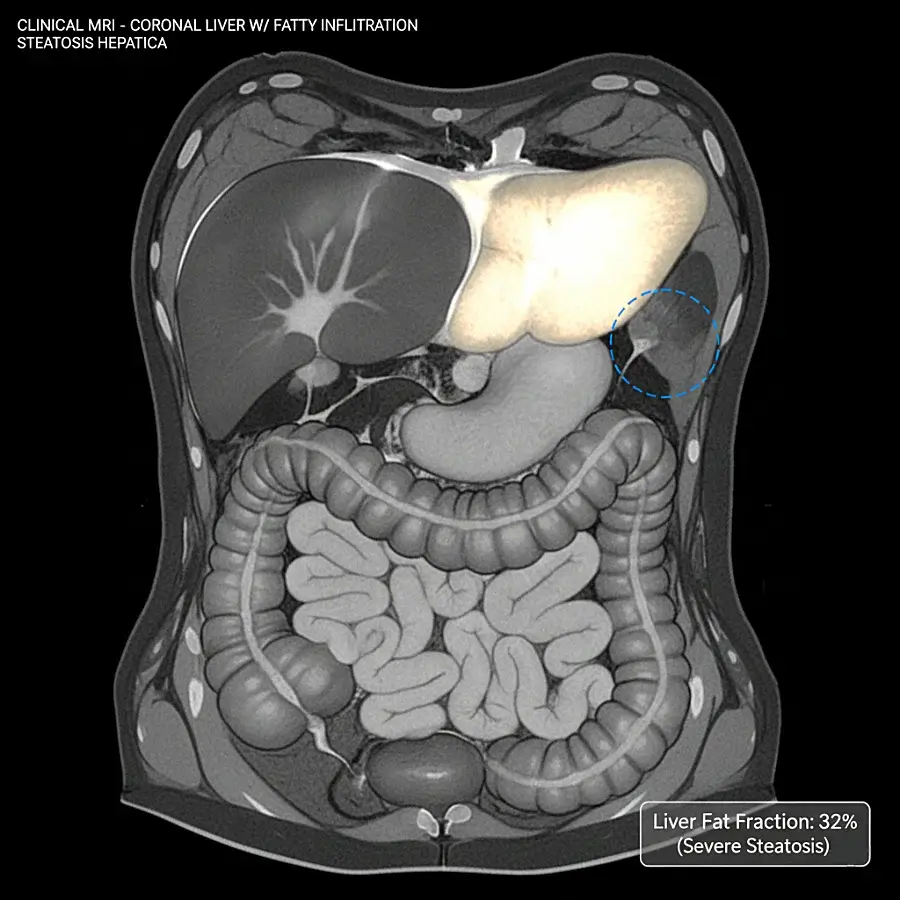

2. Ressonância magnética com quantificação da gordura

Entre os exames disponíveis, a ressonância magnética com quantificação da gordura é hoje o método que oferece a maior precisão para medir a proporção de gordura no fígado.

Ela permite:

- Quantificar o grau de esteatose com grande exatidão;

- Detectar alterações precoces;

- Diferenciar quadros simples de casos associados à inflamação.